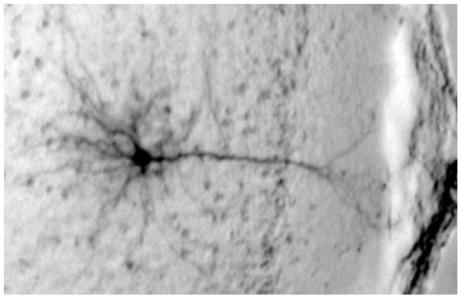

La preuve chez la souris : chez les souris qui s’adonnent à l’excès d’alcool, certains neurones du cortex préfrontal, deviennent incapables de maintenir leur activité, et la mémoire de travail se délite. Des données qui concordent avec les données d’études d'imagerie, qui montrent une diminution de l'activité de la zone, au repos, chez les alcooliques et les buveurs excessifs. Plus simplement, ces résultats illustrent pourquoi les adolescents ont des problèmes de mémoire, mais ils suggèrent aussi qu'il existe des moyens d'intervenir. Les épisodes de binge drinking altèrent l'excitabilité des neurones (visuel ci-dessus) en interférant avec les canaux qui permettent aux ions de s'écouler dans les neurones.